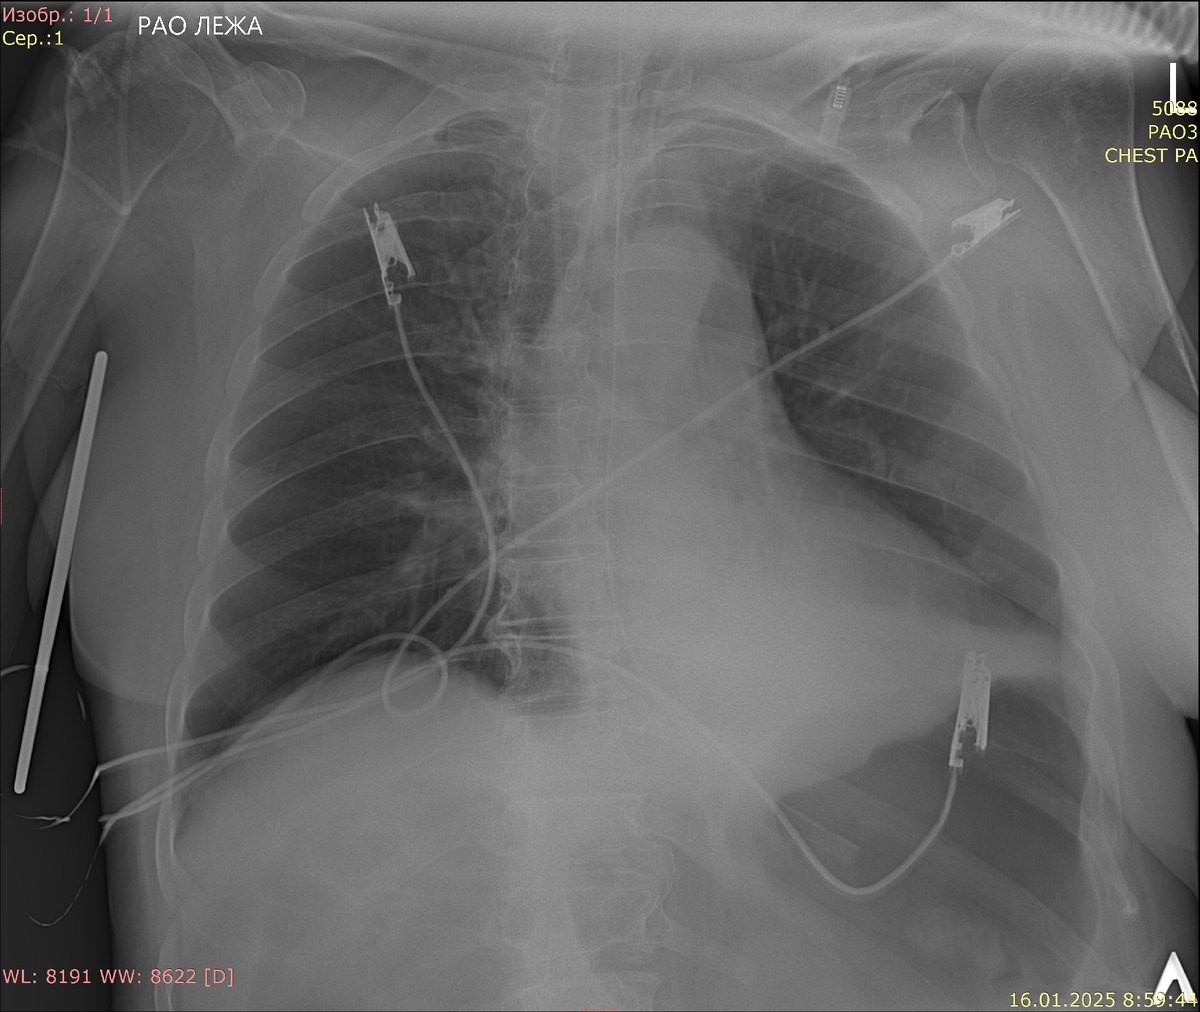

Центральные венозные катетеры (ЦВК) играют ключевую роль в современных медицинских практиках, обеспечивая доступ к центральной венозной системе для различных терапевтических и диагностических процедур. Однако правильная установка и последующая визуализация ЦВК имеют первостепенное значение для предотвращения осложнений и обеспечения эффективного лечения. В этом контексте рентгенография становится незаменимым инструментом для оценки положения катетера и обнаружения возможных ассоциированных осложнений. На рентгеновских снимках ЦВК визуализируются как тонкие линейные структуры, которые могут проходить от места введения (например, яремной или подключичной вены) до правого предсердия, где они должны правильно размещаться для обеспечения оптимального функционирования. Ключевыми аспектами, на которые врачи обращают внимание при интерпретации рентгенограмм, являются: Важно отметить, что регулярный мониторинг и периодическая рентгенография катетеров являются стандартной практикой в отделениях

Центральные венозные катетеры (ЦВК) играют ключевую роль в современных медицинских практиках, обеспечивая доступ к центральной венозной системе для различных терапевтических и диагностических процедур. Однако правильная установка и последующая визуализация ЦВК имеют первостепенное значение для предотвращения осложнений и обеспечения эффективного лечения. В этом контексте рентгенография становится незаменимым инструментом для оценки положения катетера и обнаружения возможных ассоциированных осложнений.

На рентгеновских снимках ЦВК визуализируются как тонкие линейные структуры, которые могут проходить от места введения (например, яремной или подключичной вены) до правого предсердия, где они должны правильно размещаться для обеспечения оптимального функционирования. Ключевыми аспектами, на которые врачи обращают внимание при интерпретации рентгенограмм, являются:

1. Положение катетера: Идеальное расположение ЦВК синдрома осуществляется вблизи передней стенки правого предсердия. Рентгенограмма позволяет врачу убедиться, что кончик катетера находится в правильной области, что минимизирует риск тромбообразования и травмирования сосудов.

2. Оценка состояния сосудов: Рентгеновские снимки также используются для визуализации вен, в которые вводился катетер. Наличие признаков разрывов, тромбообразования или других изменений может быть замечено на этих изображениях. Это позволяет врачам принимать решения о необходимости дальнейшей терапии или вмешательства.

3. Поиск осложнений: При изучении рентгенограмм можно выявить потенциальные осложнения, такие как пневмоторакс, который может возникнуть в результате травмы легких, или возможные крошечные воздушные эмболии, попадающие в венозное русло. Визуализируя органы, такие как легкие, врачи могут обнаружить аномалии, указывающие на необходимость немедленного вмешательства.

Важно отметить, что регулярный мониторинг и периодическая рентгенография катетеров являются стандартной практикой в отделениях интенсивной терапии и стационарах, чтобы гарантировать долгосрочную безопасность и эффективность терапии. Порядок установки и контроль за состоянием ЦВК включает внедрение строгих протоколов стерильности и обучение персонала, что позволяет минимизировать случаи осложнений, которые можно было бы легко обнаружить на ранних стадиях с помощью рентгенографии.